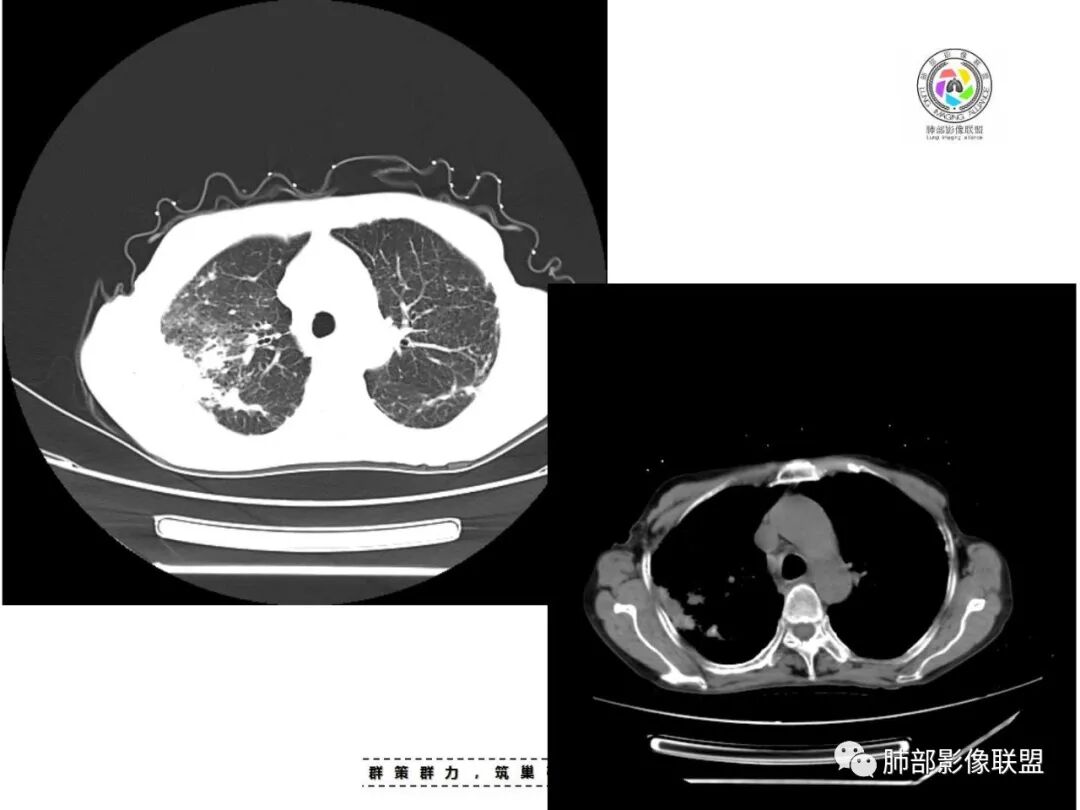

双肺多发片状影,索条影及小结节影,并见少许钙化,右肺上叶为主,主病灶无彭隆,考虑结核可能大

双肺不均匀散在分布斑片状,条索状,斑点状影,边缘部分清晰,可见部分病灶钙化,考虑感染性病变,结核?NTM?详细询问病史,尘肺+结核?

双上肺多发片状、索条影及小结节影,并见少许钙化,右肺上叶后段肿块,后段支气管阻塞,边缘膨隆,双上肺小叶间隔增厚呈多发结节状,胸膜局限性增厚,考虑:1、双肺上叶结核;2、右肺上叶后段腺癌并癌淋。

老年女性,短病程,咳嗽,咳痰为主诉,双肺多发病灶,右上为主,实变,小结节,条索,考虑结核,但小叶间隔增厚,胸膜下多发结节,警惕肿瘤。

女,67,咳嗽咳痰半月,双肺多发病灶,部分钙化,右肺为著,右肺上叶大片实变影,累及胸膜,右肺上叶支气管堵塞,右侧肺门略增大,考虑肺癌,双肺结核。

老年女性,主病灶在右肺上叶,有点散,周围可见卫星灶及少许树芽,双肺多发索条、结节及散在钙化,纵隔及肺门见钙化淋巴结,考虑结核。

双肺多发斑片,索条及结节影,内可见钙化,右肺上叶后段支气管截断,断端圆钝略扩张,双肺门及纵膈淋巴结钙化,双侧胸膜增厚伴钙化。首先考虑结核。右肺上叶亚段气管分叉处结节,警惕肿瘤

老年女性,双肺索条纤维影,右肺上叶散在卫星灶,树芽征,小叶中心融合,右肺后段支气管圆形截断,实变病灶内支气管扩张,考虑结核。

老年女性,病史半个月,两肺上叶为主病灶,多发不规则实变影、条索状影及散在小结节影,首先考虑结核,警惕合并肺癌,尤其是右肺上叶团块实变影。还可以看看重建图像,必要的增强。

患者老年女性,咳嗽、咳痰半月余。查体双肺可闻及痰鸣音。胸部CT:双肺上叶可见多发结节、条索、斑片实变影及小叶间隔增厚,部分见分叶、长毛刺及钙化,表面光滑,纵隔淋巴结有钙化。综合考虑良性病变,结核可能大,鉴别腺癌并癌性淋巴管炎。

老年女性,咳嗽咳痰,双肺散在片状及索条状高密度影,以右肺上叶为主,周围可见结节,实变内可见钙化,纵膈及双肺门可见钙化淋巴结,首先考虑感染性病变,结核可能大,警惕右肺上叶肿瘤并癌性淋巴管炎

双肺多发斑片,索条及结节影,内可见钙化,右肺上叶结节影,空泡,右肺上叶后段支气管截断,断端圆钝略扩张,双肺门及纵隔淋巴结钙化,双侧胸膜增厚伴钙化。首先结核肯定会有,右肺上叶结节,考虑腺癌

老年女性,咳嗽咳痰半月,肺部听诊痰鸣音。影像以右上肺实变?肿块?与支气管关系不清晰;另见两上肺结节、条索,胸膜局部增厚有钙化点,纵隔肺门淋巴结见钙化。综合考虑结核可能性大,注意肺癌。完善增强及支气管镜等检查。

老年女性,咳嗽咳痰半月,双上肺多发条索影,结节影,密度较高,右肺上叶不规则肿块,内有钙化,靠近胸膜下,靠内侧可见斑片影,树芽征,支气管壁增厚,考虑尘肺并肺结核,肺癌待排。

双肺上叶,结节,斑片,条索,大片实变影,支气管远端不通,是不是层面不够啊,后段支气管堵没堵?肺门纵隔淋巴结钙化,常规考虑结核。

双上肺索条,多发边缘清楚的结节,右上肺结节灶,无连续层面,不能判断支气管是否堵塞,双肺多发钙化,考虑结核,建议气管镜

常规考虑结核(鉴别尘肺合并结核,职业史?),老年人还要排除恶性(原发肺癌或者转移,需要结合病史与肿瘤标志物,必要时穿刺活检或支气管镜检)

双肺多发条索状,结节病灶,以右肺显著,部分病灶有爬树征,树芽征,未见明显钙化,纵隔淋巴结增大钙化,常规考虑结核,不能排除肺癌,建议增强和支气管镜检查

两肺上叶多发索片小结节影,部分密度较高,中央间质和周围间质都增厚,肺门纵隔淋巴结肿大钙化,基础疾病考虑有尘肺或陈旧结核,需结合相关病史;右肺上叶见斑片点片状模糊影,部分树芽征上叶后段局部细支气管闭塞,考虑感染,结核可能性大,右肺上叶后段病灶实变成团块状,密度低于胸壁肌肉,首先还是考虑结核肉芽肿,治疗后复查除外合并肿瘤可能。

老年女性,67岁,咳嗽、咳痰半月余。双肺可闻及痰鸣音。

胸部CT:双肺上叶多发小结节,沿胸膜下、支气管血管束分布。右上肺斑片实变影、索条影及小叶间隔不均匀增厚,支气管枯枝征?纵隔淋巴结多发肿大,部分有钙化。综合考虑:结节病?尘肺?鉴别:腺癌并癌淋。

1.双肺片状影、大小不等斑片影、结节影、树芽等,病灶密度偏高多钙化。

2.病灶上肺为主,胸膜下分布为主。双肺病灶明显不对称,右肺块状影较大。

3.纤维条索影广泛杂乱、牵拉,横向分布为主,这点给人也印象很深!

4.纵隔轻度右移。双肺门纵隔淋巴结增大钙化。

5.老年女性患者,咳嗽咳痰半月余